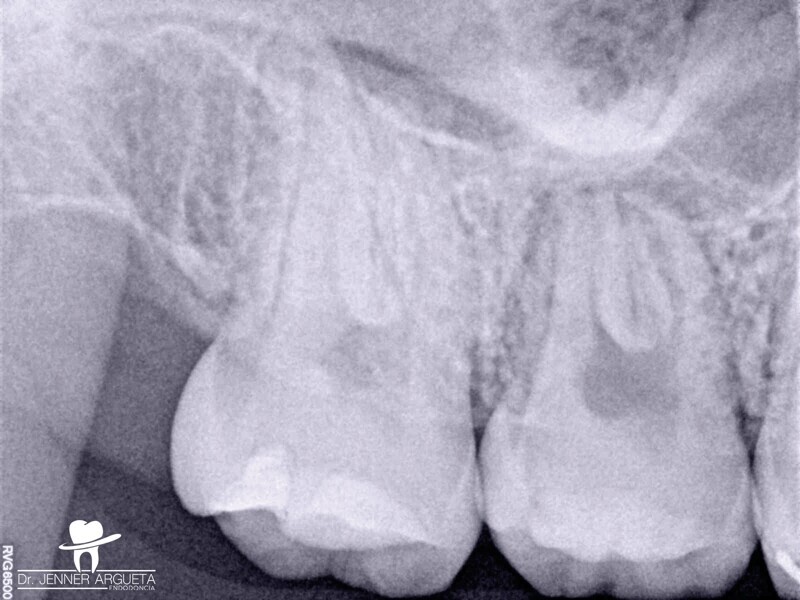

L’utilisation d’un ciment de scellement endodontique à base de silicate de calcium facilite le processus d’obturation, et l’activation ultrasonique permet de distribuer le matériau sur toute la longueur du système des canaux radiculaires nettoyés et mis en forme (Fig. 9). Une restauration coronaire adhésive a été effectuée dans le cadre de la même visite au moyen d’un matériau de reconstitution corono-radiculaire à double polymérisation (NexCore, Meta Biomed) pour la cavité pulpaire et d’un composite compactable pour la surface occlusale (Ezfi l, Meta Biomed ; Figs. 10a et b). La dent était fonctionnelle et asymptomatique, et la patiente a dès lors pu commencer son traitement orthodontique. La radiographie prise à l’occasion du suivi à trois ans a montré un tissu périapical sain (Fig. 11).

Fig. 11 : Radiographie de suivi après trois ans. La zone périapicale est cicatrisée.